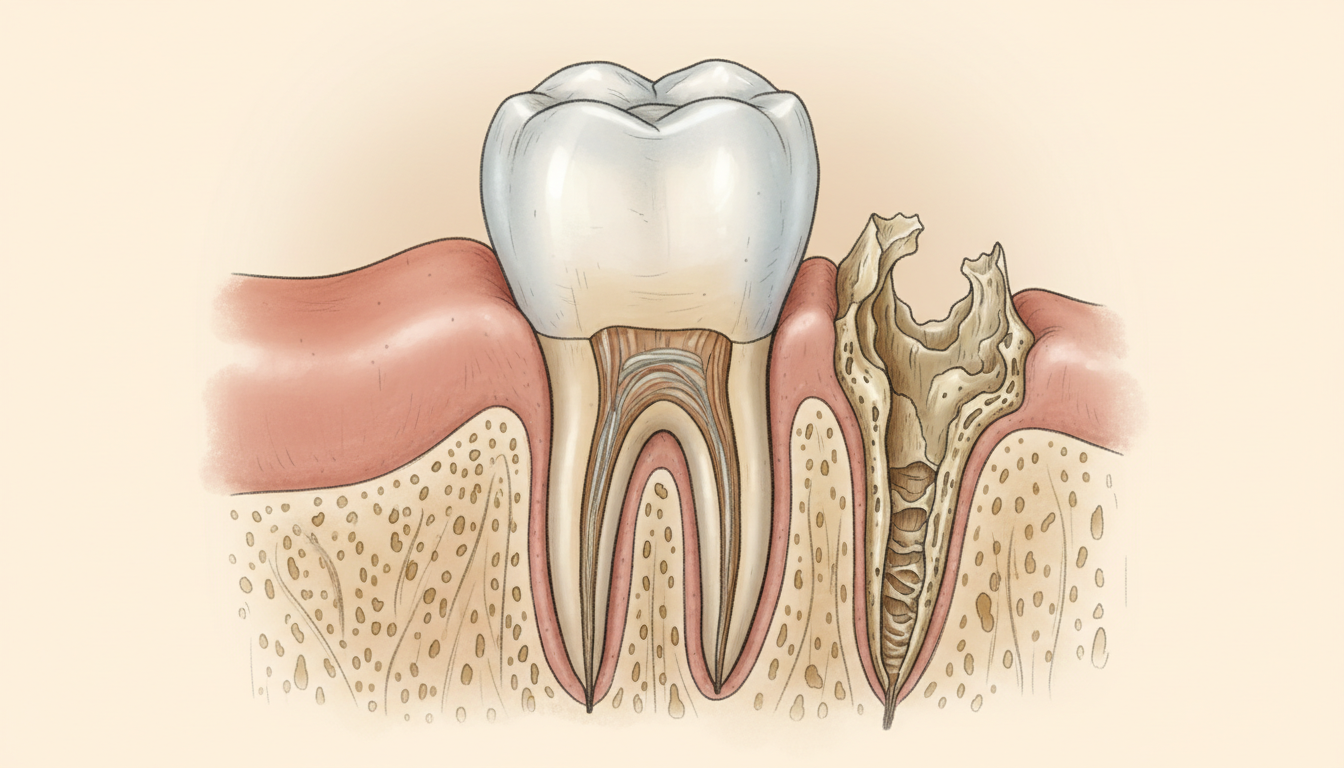

顎の骨(歯槽骨)が吸収される

これが、放置による最も深刻なリスクのひとつです。

歯の根は、噛む力を顎の骨に伝える役割を担っています。歯が失われると、その部分の骨に刺激が届かなくなります。骨は刺激がなければ少しずつ吸収(やせていく)されていきます。

歯槽骨の吸収…

歯を支えていた顎の骨が、歯を失った後に徐々に減少していく現象。吸収が進むと、インプラント治療に必要な骨の量が不足し、骨造成(こつぞうせい)などの追加処置が必要になることがあります。

骨の吸収は、歯を失った直後から始まります。放置すればするほど骨は減り、将来の治療の選択肢が狭まっていきます。